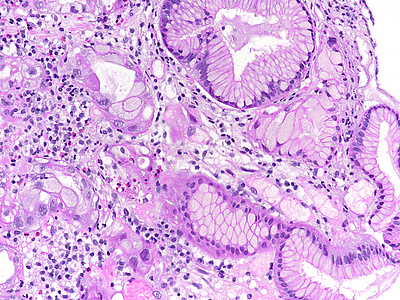

A 41-year-old female with ocular malignant melanoma, metastatic to both lobes of the liver, presented with nausea, vomiting and epigastric pain. Upon endoscopy, a large ulcerated lesion, extending from the corpus to the duodenal bulb, was detected (Panel A). Upon histology, ballooning cells with mild to moderate nuclear atypia were observed within the surface and foveolar epithelium (Panel B-C). Marked nuclear pleomorphism, hyperchromasia and loss of polarity, along with increased cytoplasmic eosinophilia were present within the deep gastric glands (Panel D). Mitotic figures were not seen, and  the  Ki-67 labelling index was low (Panel E). p53 overexpression was noted in the atypical cells, however with  heterogeneous staining, thereby indicating an activated wild-type pattern (Panel F).

The presented case demonstrates severe atypia of the gastric epithelium, which exceeds what is typically seen in ischaemic injury and may lead to the erroneous diagnosis of dysplasia and/or malignancy. Drug toxicity explains these findings. Specifically, fotemustine causes interstrand crosslinking of DNA, which prevents DNA replication, and ultimately leads to apoptosis in a p53 dependent manner. Interestingly, Ki-67 labeling was low in our case. This may be attributable to the fact that the highest levels of nuclear Ki-67 staining are reached during the M phase of the cell cycle, which the epithelial cells failed to enter due to the drug effect (Varelas et al. 2022).